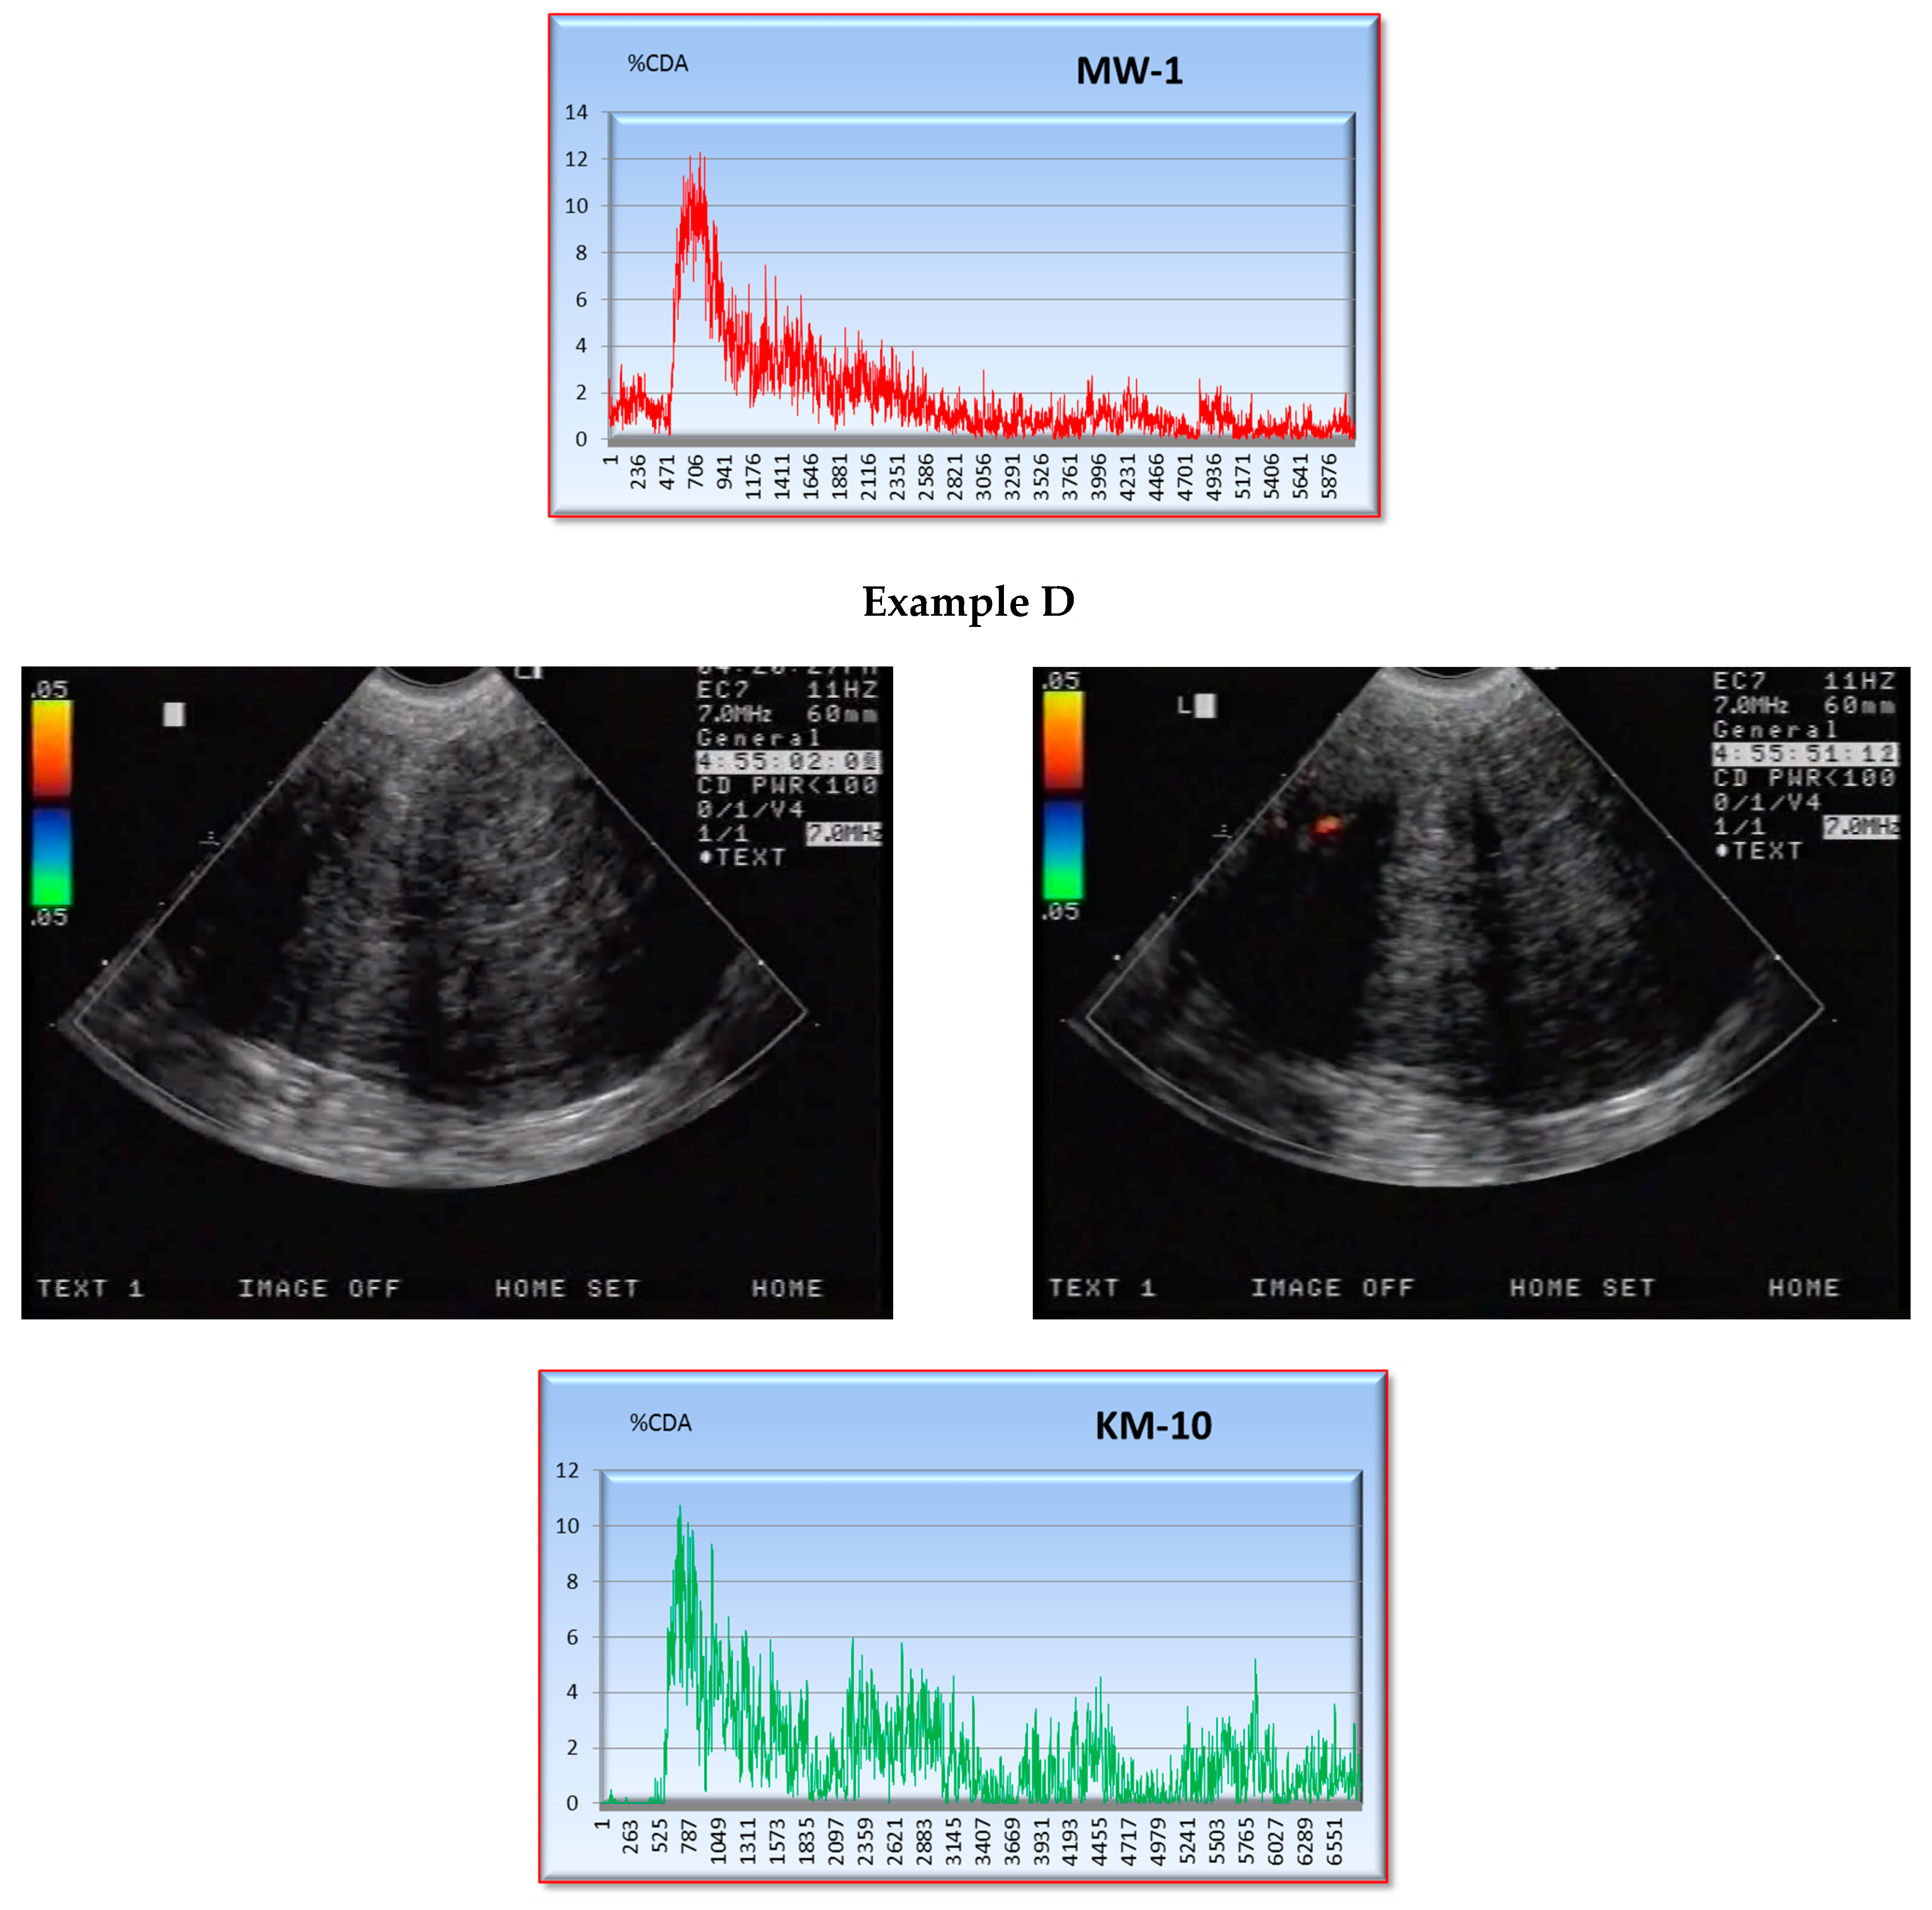

2.2. CEUS

3.1. S Parameter

3.2. Correlation of the S Parameter with CD34-, CD105- and BCL2-Expression Levels